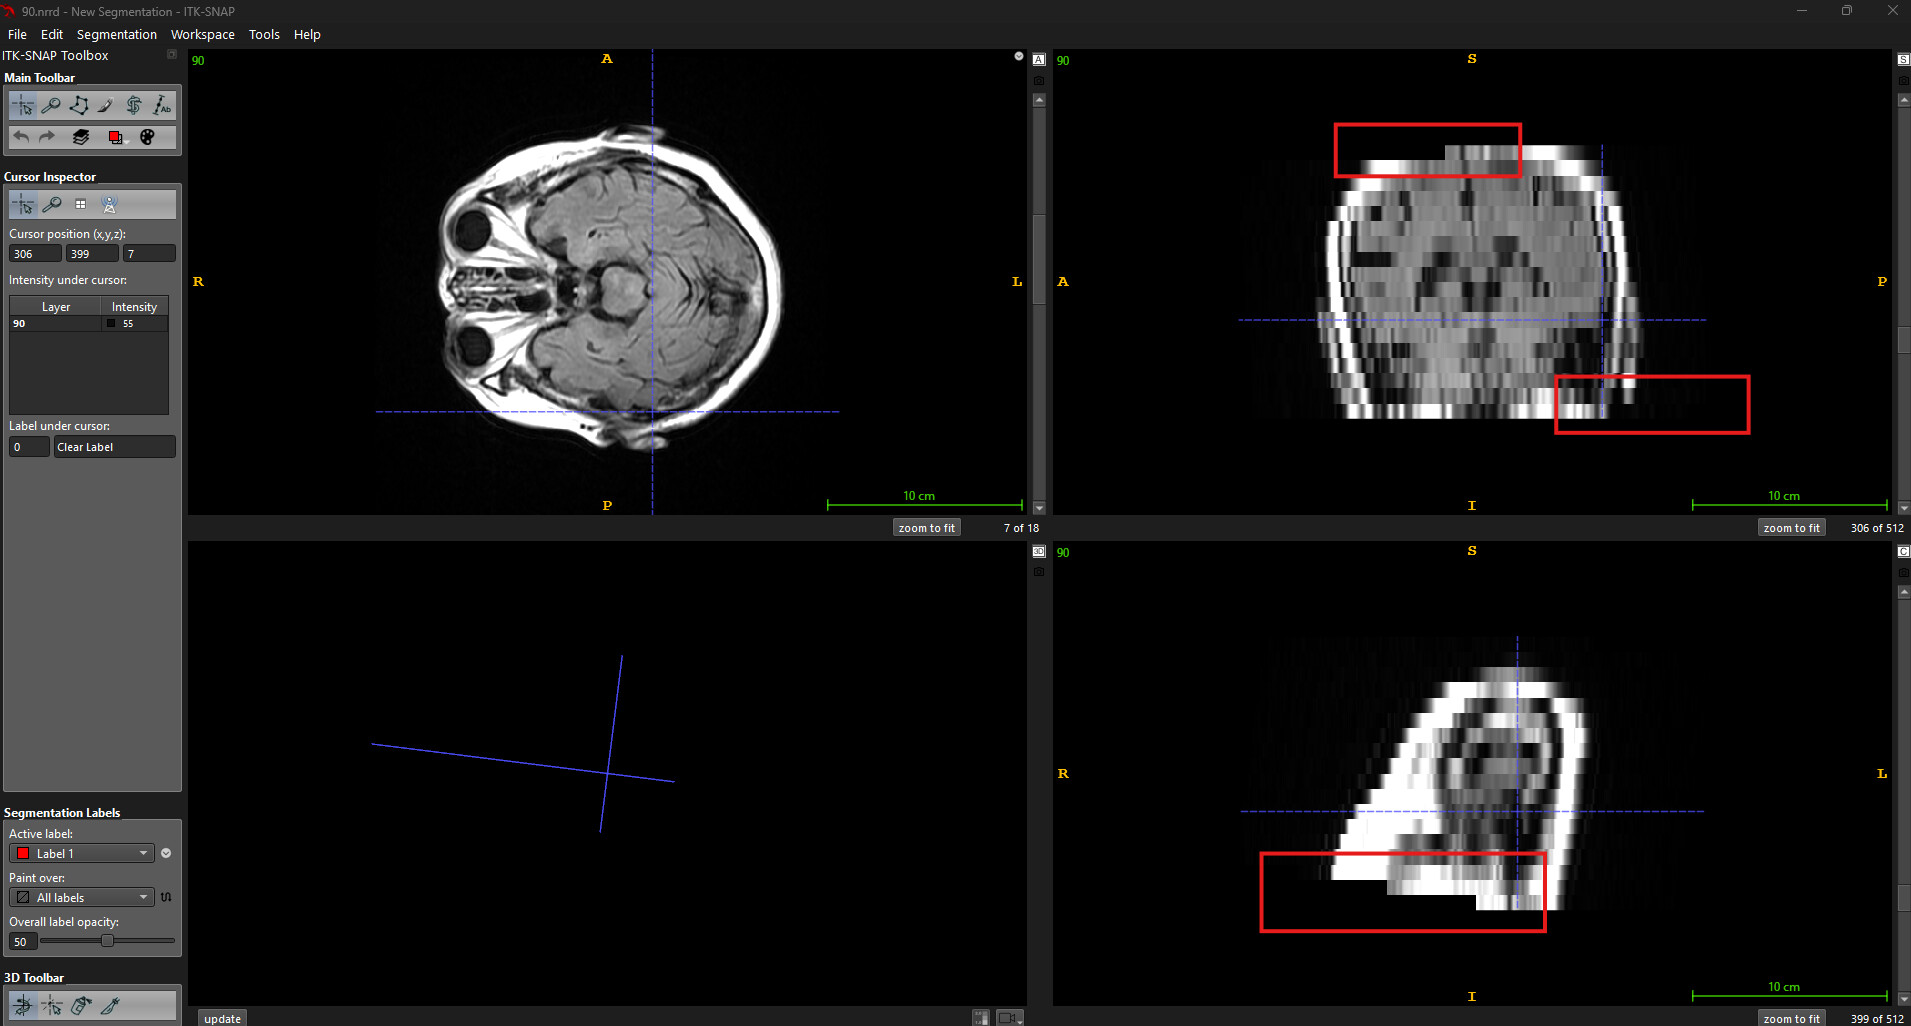

But when, instead of rotating using C++ code, if I rotate my axial volume in the ITK-SNAP app, the image is proper, as we can see in the image below.

ITK-SNAP Rotate output: